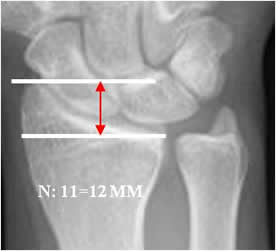

La longitud radial:

Líneas paralelas entre borde final de la apófisis estiloides y el borde inferior de superficie articular. El valor normal es de 11 a 12 mm y se altera en fracturas. (12). (Fig 47 y 48).

Fig 47. Longitud radial normal.

Rx AP. Distancia entre las líneas que pasan por el extremo de la apófisis estiloides del radio y la superficie articular.